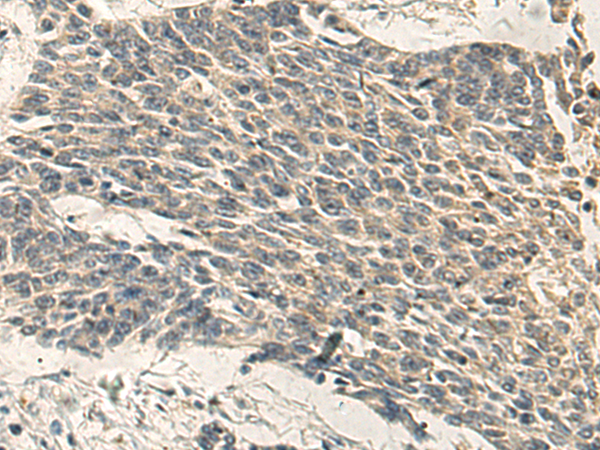

The image is immunohistochemistry of paraffin-embedded Human colorectal cancer using (PRKCH Antibody) at dilution 1/35.

The image is immunohistochemistry of paraffin-embedded Human gastric cancer using (PRKCH Antibody) at dilution 1/35.